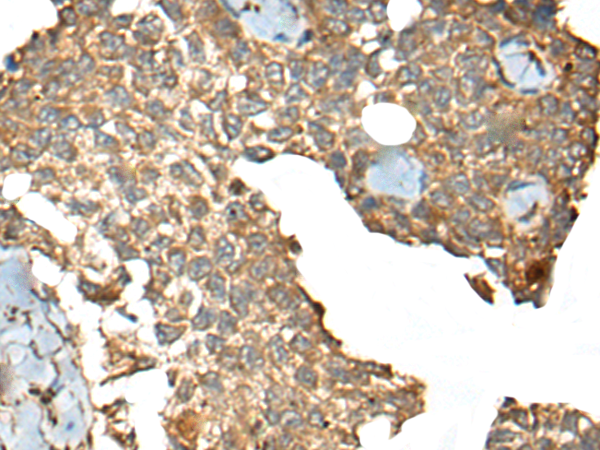

IHC positive control: |

Human ovarian cancer and human esophagus cancer |

IHC Recommend dilution: |

30-150 |